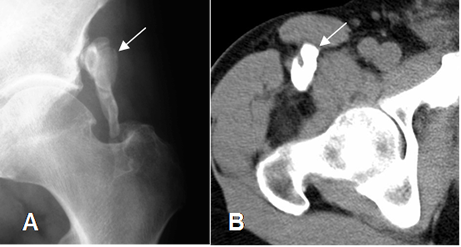

Fig 210B. Miositis osificante.

A: Rx de cadera y B: TAC axial. 2 casos diferentes donde existe calcificación de tejidos blandos en relación con grupos musculares, por miositis osificante.